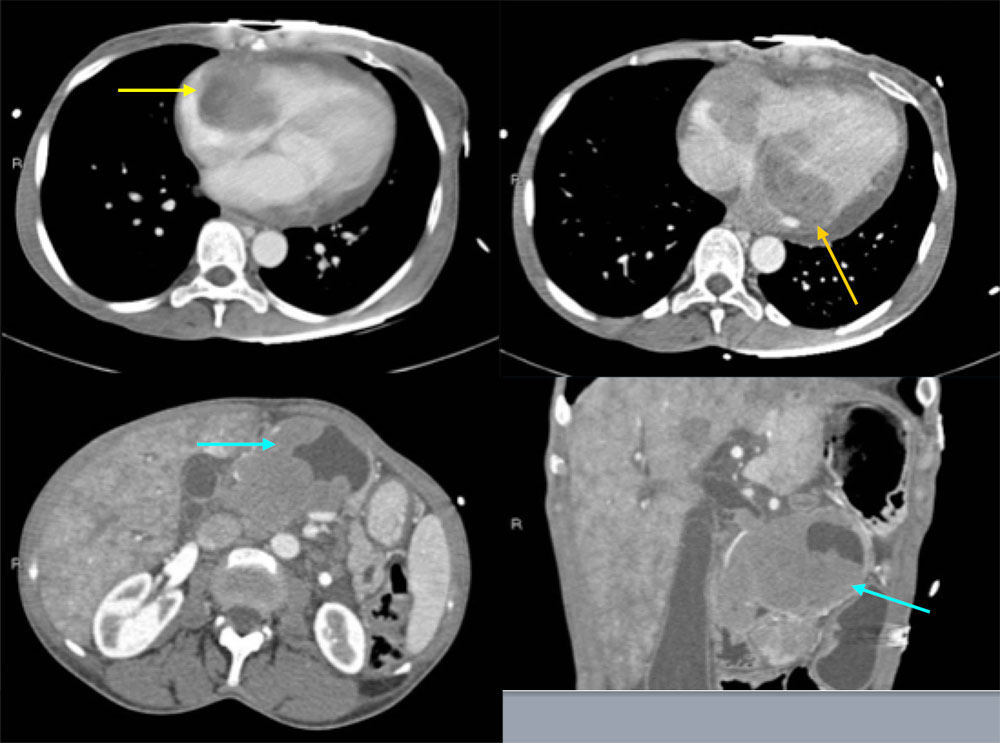

49 year old female with poorly controlled HIV/AIDS with chest and epigastric pain The axial CT images at the level of the heart demonstrate masses infiltrating both the right and the left atria. The axial and coronal CT images at the level of the abdomen demonstrate a large, part cystic and part solid mass within the pancreas. Biopsy of this pancreatic mass was positive for Burkitt lymphoma. ![]() |